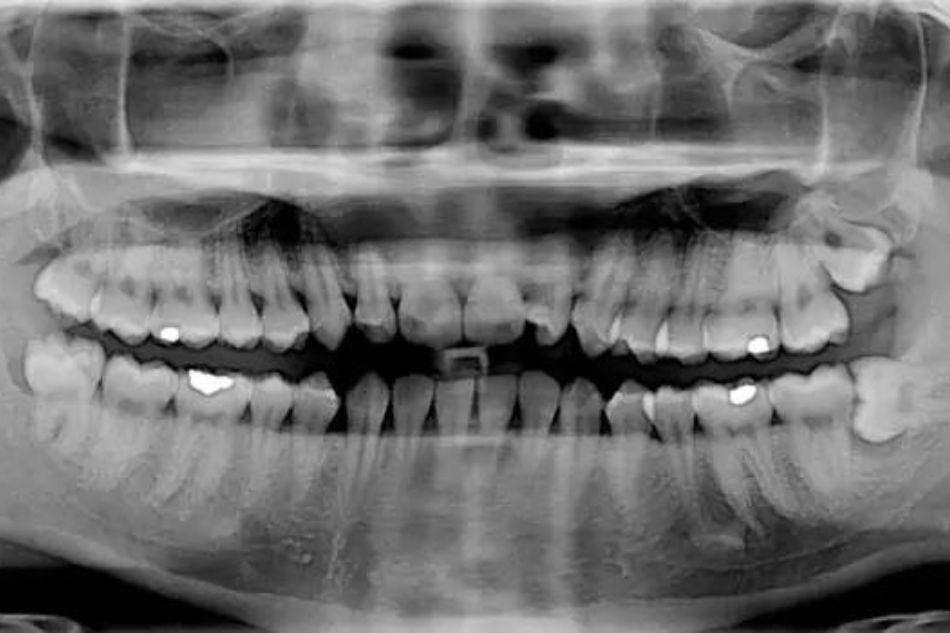

Perché eseguire una panoramica dentale ad alta definizione

L’ortopantomografia (OPT), detta anche panoramica dentale, è un esame radiologico che permette lo studio delle arcate dentarie superiori ed inferiori e delle ossa mascellari e mandibolari.